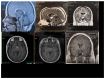

Case presentation: A 20-year-old patient was admitted for the evaluation of growth delay and hyperphagia. HbA1c level and fasting blood glucose were in the normal range. The diagnosis of hypothalamopituitary histiocytosis was based on histological features after biopsy of a large suprachiasmatic lesion identified on magnetic resonance imaging (MRI). Association of vinblastine and purinethol was started followed by a second-line therapy by cladribine. During the follow-up, the patient was admitted for recurrence of hyperglycemic states and extreme insulin resistance. The screening for serum anti-insulin receptor antibodies was positive. Each episode of hyperglycemia appeared to be correlated with tumoral activity and increase in serum anti-insulin receptor antibodies and appeared to be improved when the disease was controlled by chemotherapy.